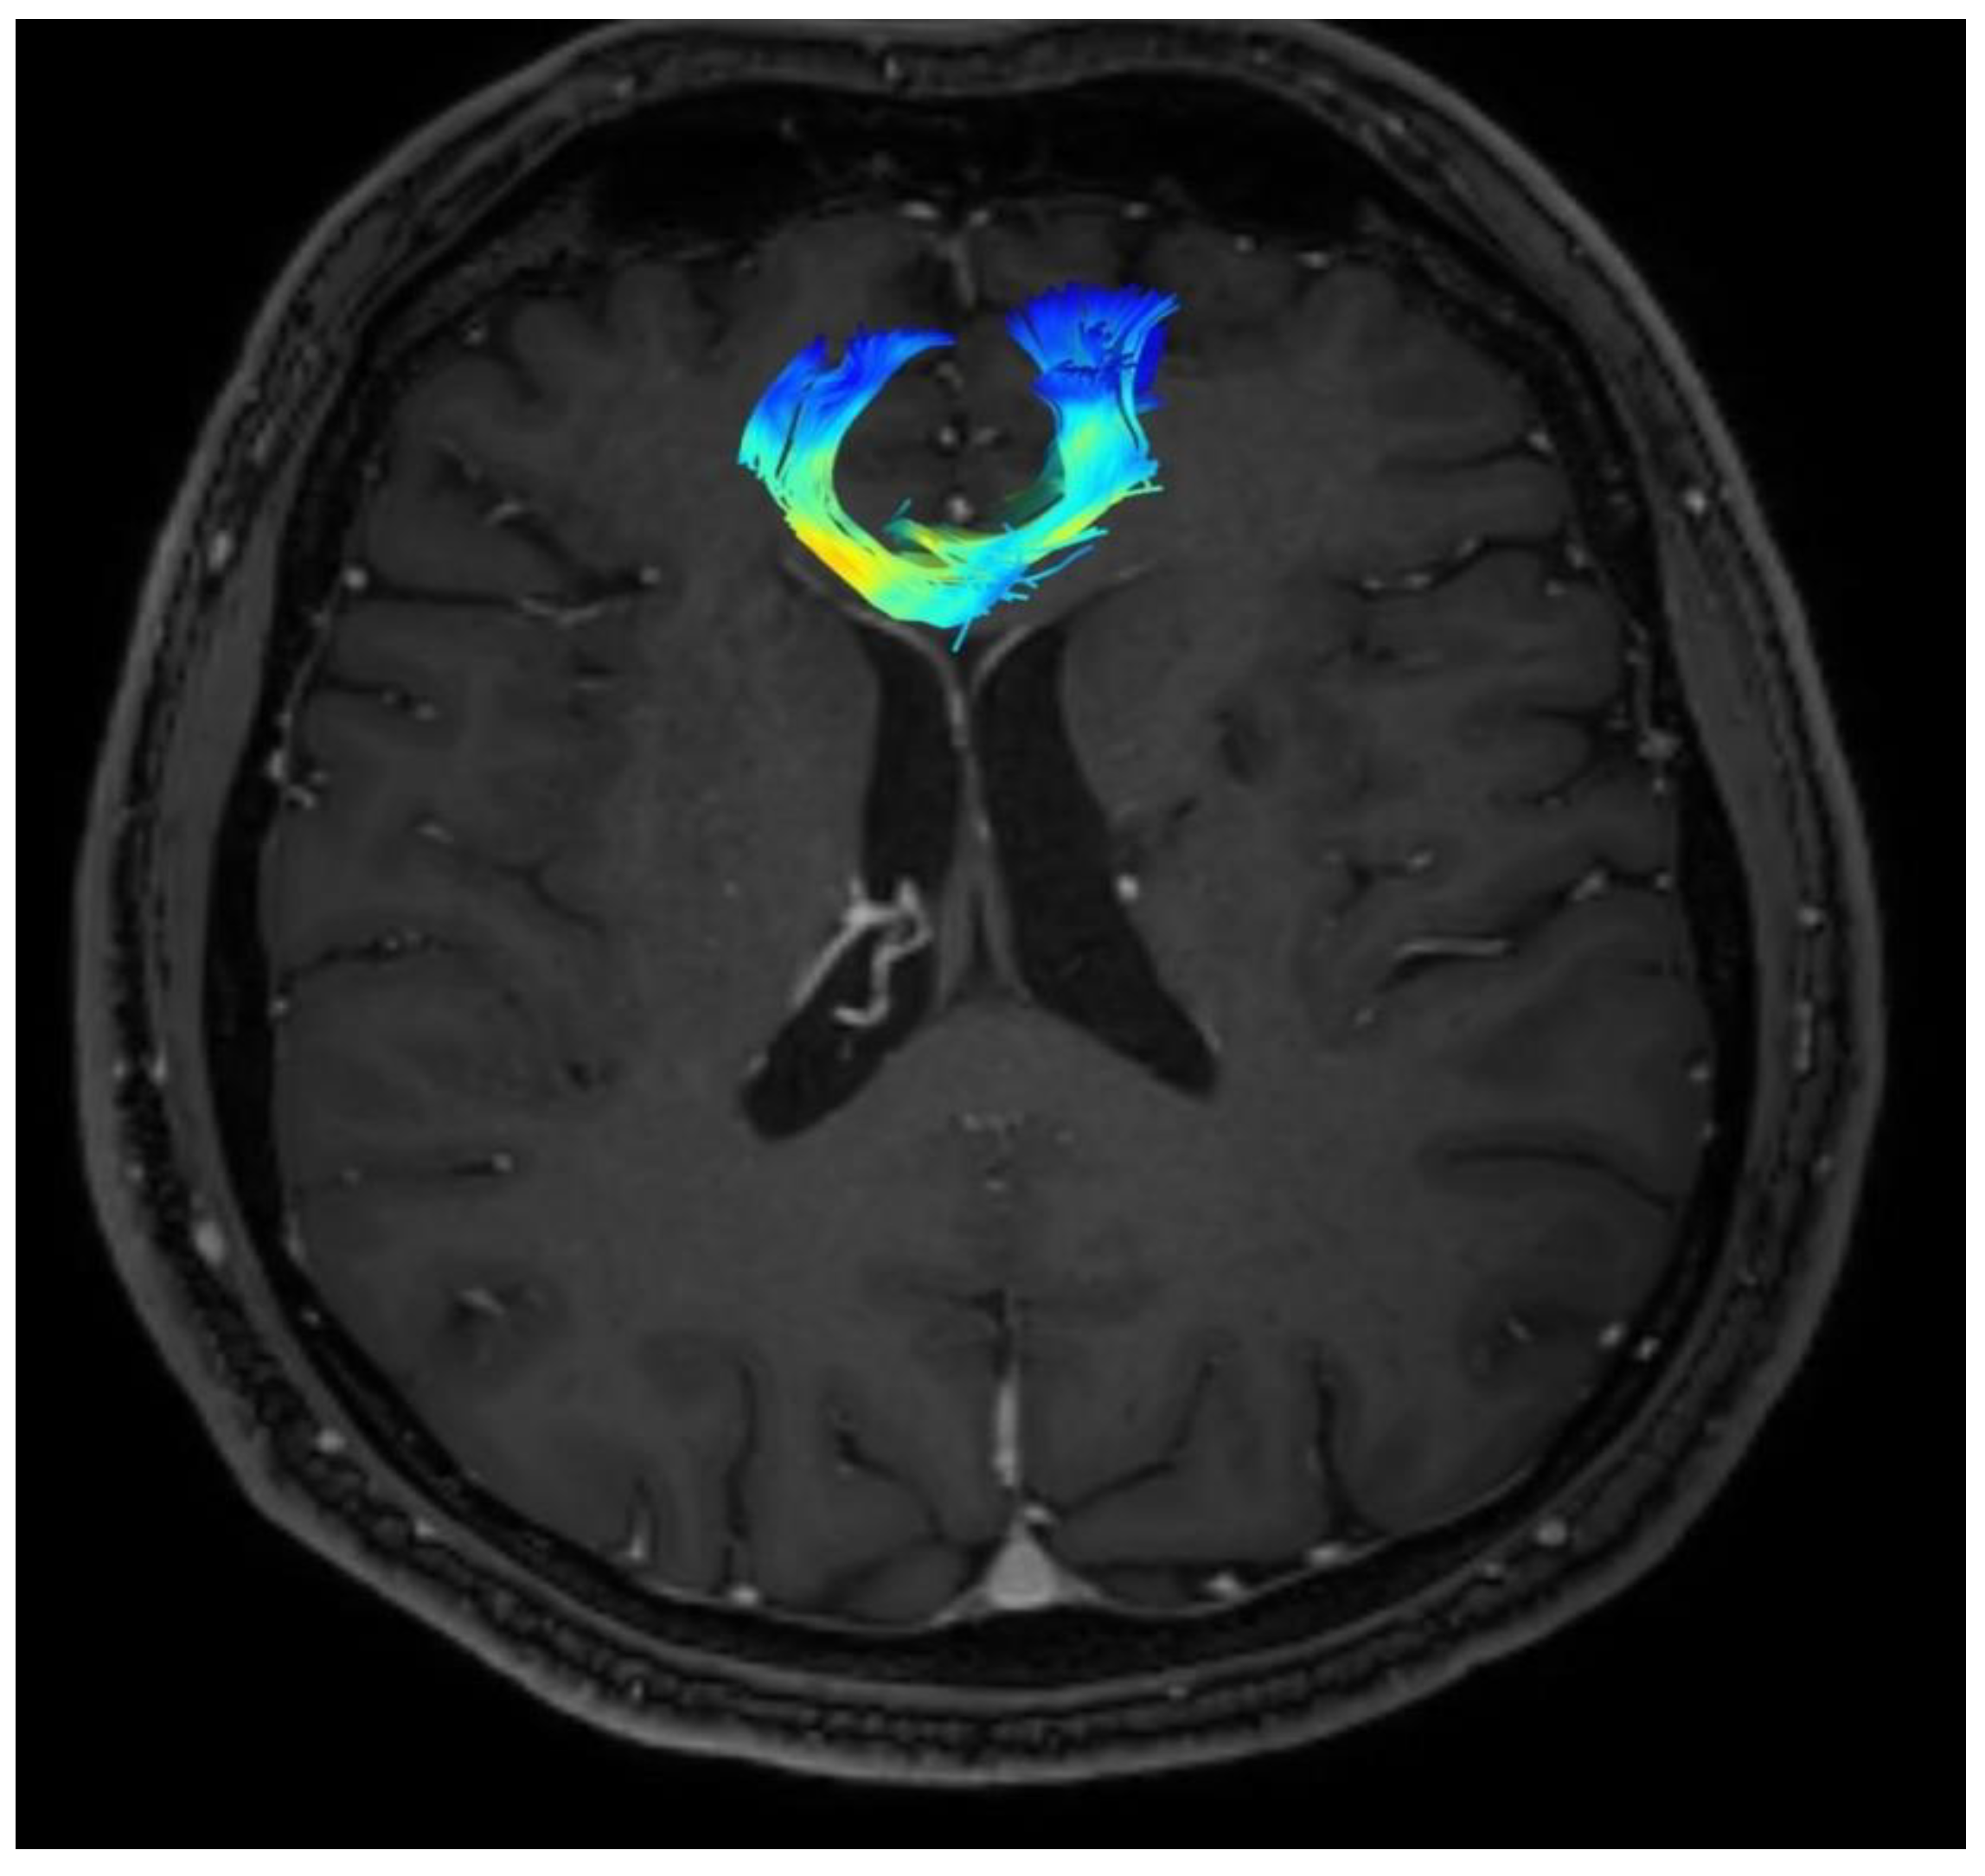

Changes in the anatomy of forceps minor before and after cingulotomy are presented in Figure 2 and Figure 3; moreover, arcuate fasciculus before and after cingulotomy is presented in Figure 4 and Figure 5.

Figure 4. Arcuate fasciculus before cingulotomy.

Brainsci 13 00044 g004